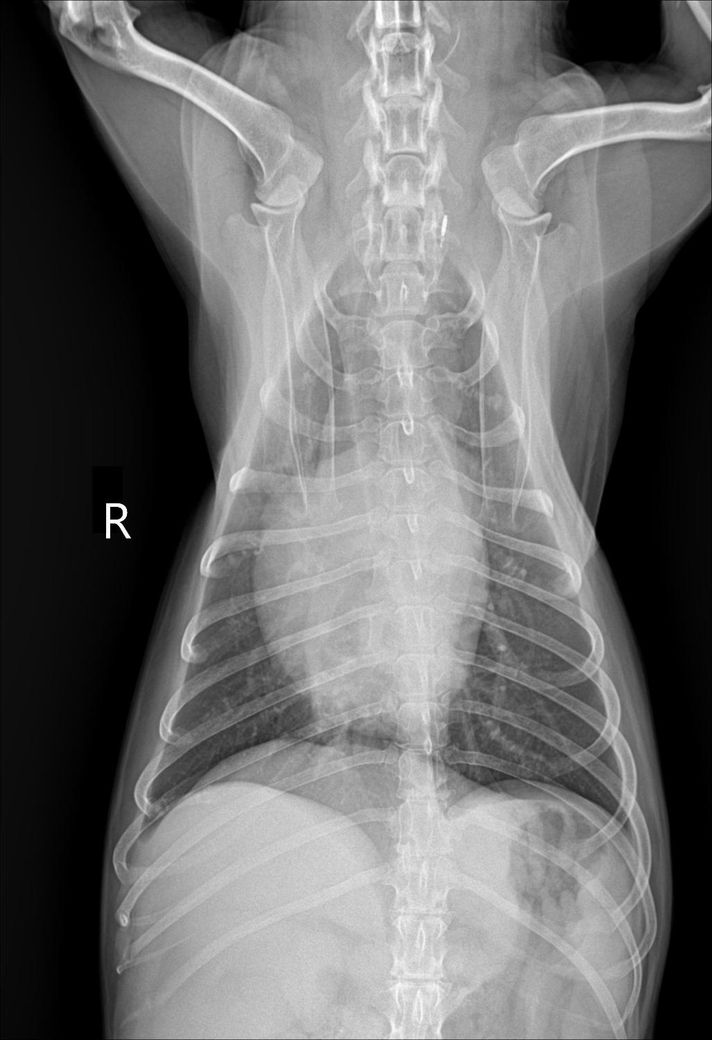

간크기 작다고 하는데 어디를봐야 작은걸 알수있을까요?? 정말 간이 작은 편인건도 궁금합니다!!

믹스(중성화o), 몸무게9.3kg 입니다